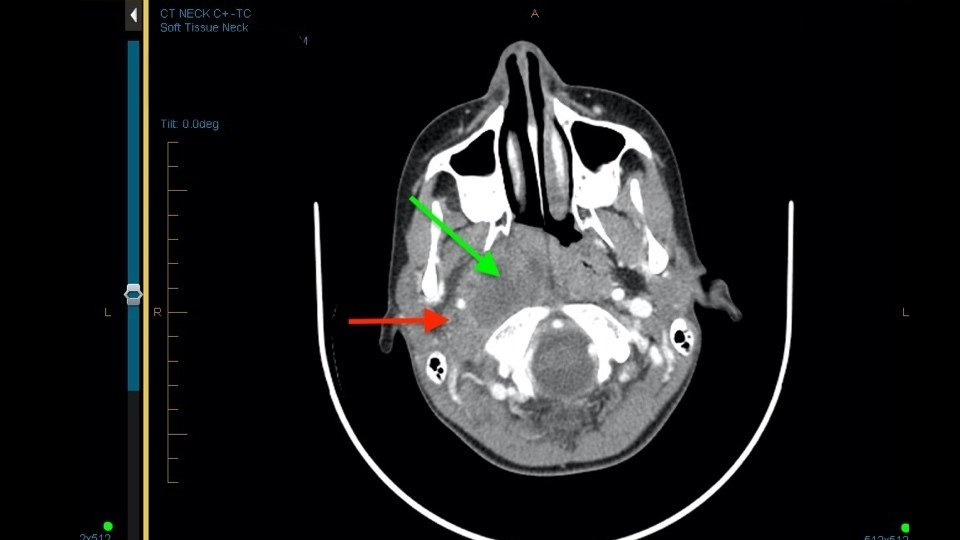

The ophthalmology team suggested computerised tomography (CT) imaging of the brain was indicated and, if negative for acute pathology, the patient could be reviewed as an outpatient. The neurology team also suggested a CT brain and, if this were negative, no further neurology input would be needed at this time. A CT angiogram demonstrated a large (52mm TR x 50mm AP x 49mm CC) right, homogenously hyperdense paraclinoid frontal lobe mass (Figure 1). Involvement of multiple intracranial arterial vessels was noted including narrowing and medial displacement of the right supraclinoid internal carotid artery (ICA), posteromedial displacement of the right M1 middle cerebral artery (MCA), non-enhancement of right M2 MCA (with surrounding collateral vessel enhancement) and displacement of the anterior cerebral arteries (ACA). This scan also demonstrated compression of the right optic nerve, global sulcal effacement, right lateral ventricle effacement, anterior and posterior clinoid process erosions and 14mm left midline shift. Given the appearance and location, a sphenoid wing meningioma was suspected.